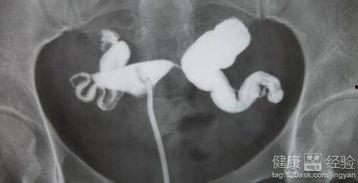

首先,得先了解什么是输卵管积水。简单来说,就是输卵管这根管道里积聚了过多的液体,就像一个装满了水的袋子,时间久了,就会变得沉重,甚至影响到生育。

5. 切除积水:医生会找到积水所在的输卵管,用手术刀将其切除,并缝合伤口。